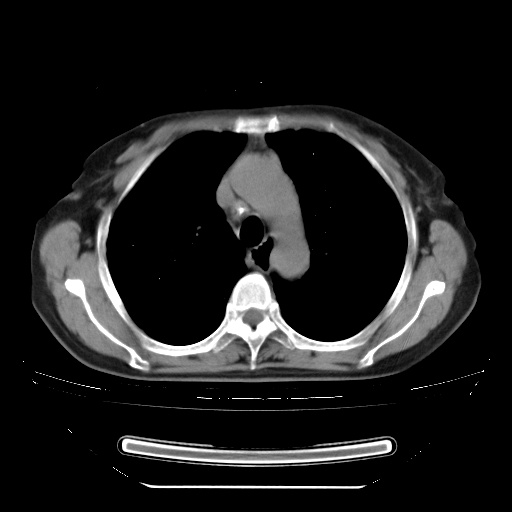

患者女性,72岁,慢性咳嗽3月余,曾抗炎治疗无效果,最近抗结核治疗约半月余,症状缓解。

ct示两肺粟粒状病灶,以两肺上叶尖后段及下叶背段分布为主;首先考虑结核。请战友们分析。

查原发灶吧,肺内转移瘤!肝内也有病灶,需强化明确。

两肺内病灶呈小结节状和树芽状,纵膈的肿大的淋巴结密度不均匀,并见有钙化,多形态病灶,考虑为两肺结核,肝内考虑小囊肿。

以下是引用zhw974247在2009-3-6 6:25:00的发言:[br]两肺内病灶呈小结节状和树芽状,纵膈的肿大的淋巴结密度不均匀,并见有钙化,多形态病灶,考虑为两肺结核,肝内考虑小囊肿。